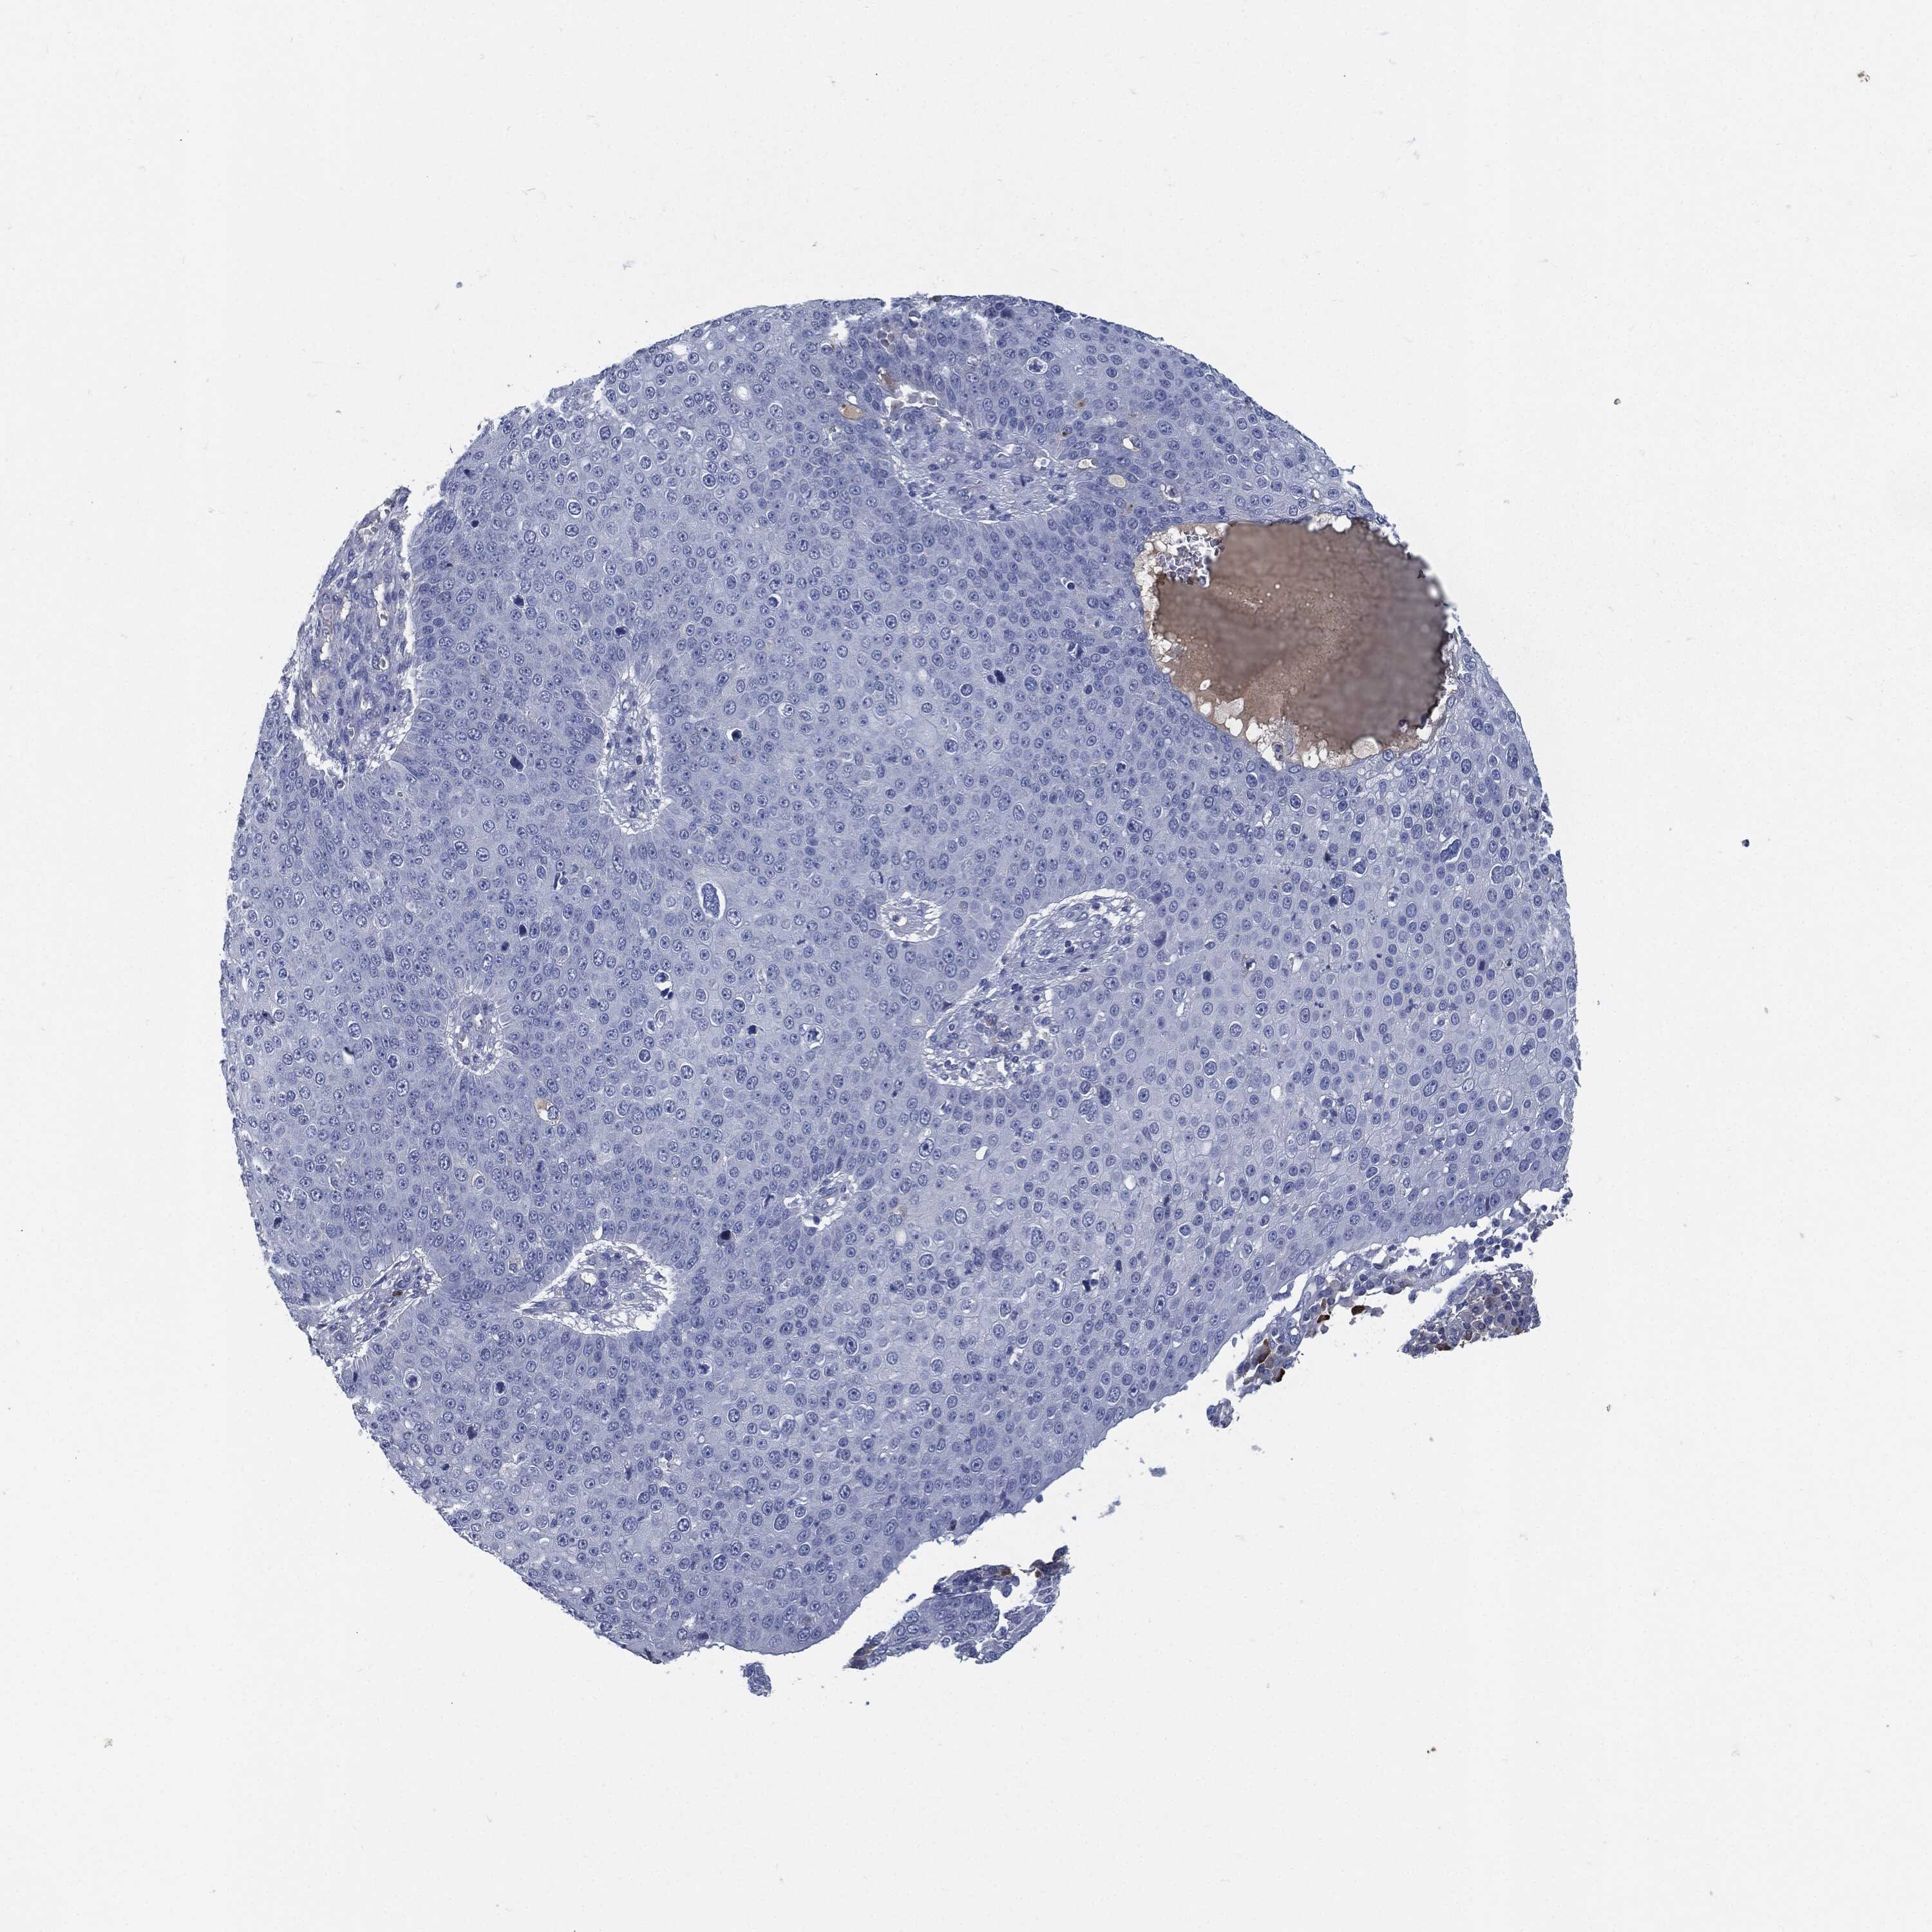

SKIN CANCER - Protein expressioni

A mouse-over function shows sample information and annotation data. Click on an image to view it in a full screen mode. Samples can be filtered based on level of antibody staining by selecting one or several of the following categories: high, medium, low and not detected. The assay and annotation is described here.

Each image is clickable and will lead to virtual microscopy that enables deeper exploration of all samples and also displays staining intensity scores, fraction scores and subcellular localization as well as patient and tissue information for each sample.

Antibody HPA038936

Basal cell carcinoma